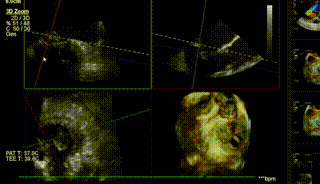

图5-7. 顶心尖确定穿刺点,跨瓣球跨瓣及寻找A-P、1-3区方向维度

图8-10. 由于反流偏3区,需在MultiVue指导下进行瓣叶捕获夹合,先植入偏3区的夹子后,再次跨瓣植入偏2区的第二枚夹子,二夹收紧后即刻可见反流降至轻度